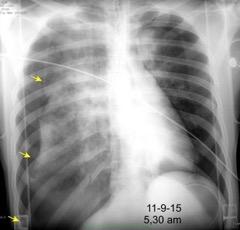

Visible en radiografías en decúbito supino de los pacientes con neumotórax por la acumulación de aire en el seno costofrénico.

“Deep sulcus sign”. Seno costofrénico aumentado en anchura y profundidad

Polireddy K et al. Blunt thoracic trauma: role of chest radiography and comparison with CT findings and literature review . Emerg Radiol 2022.

Kumaresh A et al. Back to Basics – ‘Must Know’ Classical Signs in Thoracic Radiology. Thoracic Radiology. J Clin Imaging Sci 2015.